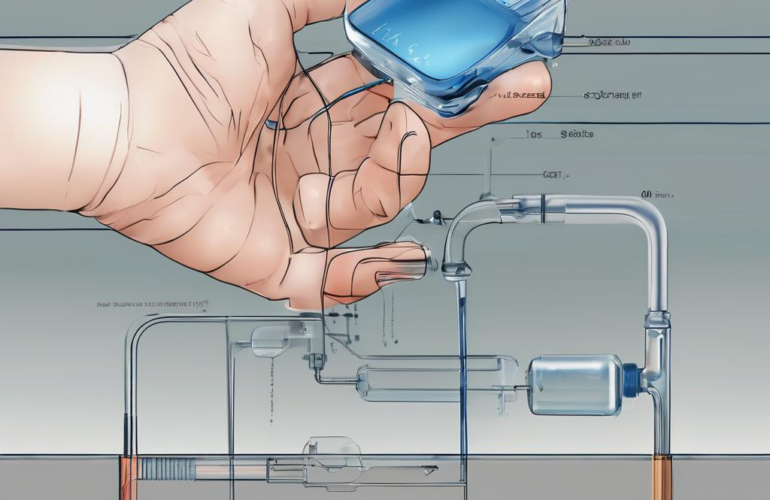

- Iontophoreseset für eine Anwendung gegen Schwitzen unter den Achseln

- Die Graphit-/Silikon-Achselelektroden passen sich optimal der Form der Achselhöhlen an

- Einfache Bedienung auch für Technik-Laien über großes, helles Grafik-Display

- Automatische Start-/Stoppfunktion bei Kontakt, bzw. Kontaktverlust

- 2 Jahre Gewährleistung – Saalio Iontophorese – made in Germany